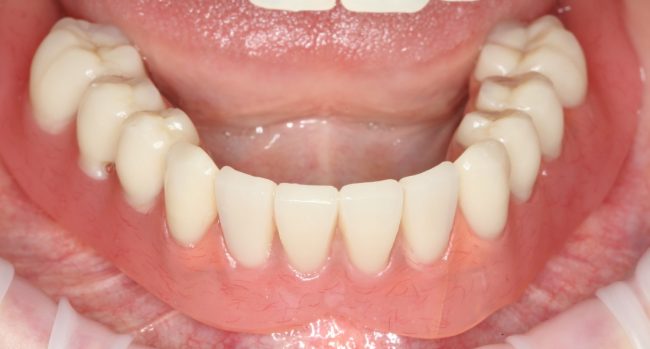

Через три месяца мы сняли коронки с имплантатов, чтобы оценить качество формирования десневого контура:

С этого момента можно перестать переживать — десневой контур сформировался правильно, мы получили достаточный объём и качество окружающей платформу имплантата десны. Можно приступать к изготовлению постоянной протетики. Подрядчиком стала зуботехническая лаборатория French Creative, одна из топовых лабораторий Москвы.

И вот, в жизни Марии наступил долгожданный день — окончательная фиксация керамических коронок на установленные имплантаты:

При этом, она ни дня не оставалась без зубов, была полностью социализирована и жила обычной жизнью. Спустя 5 месяцев после удаления, поставленную Марией клиническую задачу можно считать решёной. Но это с её точки зрения. С нашей же, всё самое интересное только начинается.